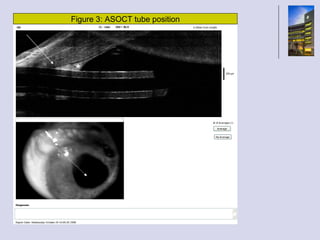

This document contains 3 figures showing different positions of an ASOCT tube. No other context or details are provided about the figures, what ASOCT stands for, or what is being imaged. The document simply lists 3 figure numbers and positions without any other accompanying explanation.